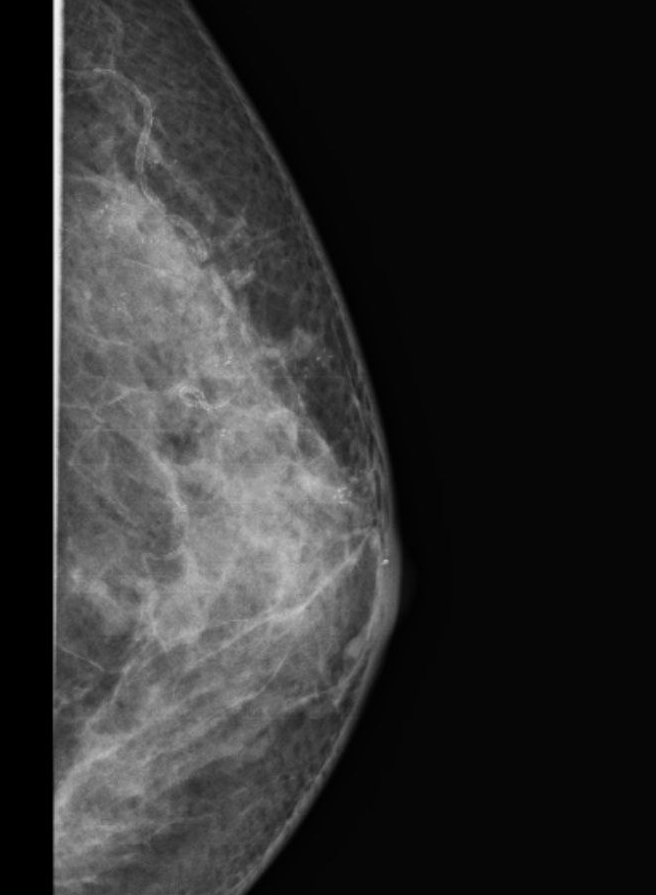

Клинический пример. Рак визуализируется на маммографии в виде скопления микрокальцинат на достаточно большой площади.

Никаких клинических изменений в виде изменений кожи, выделений из соска, у пациентки не было. Она обратилась в РНЦРР.

На рисунке есть множественные микрокальцинаты - проявления болезни внутри протоков. Выявлено два участка.

К сожалению, данной пациентке не удалось сохранить ареолу с соском во время операции, так как центральные протоки соска задействованы в онкологическом процессе. На первом этапе установлен тканевой расширитель. Затем будет имплант.

Наглядный пример того, что маммологические скрининговые обследования должны выполнятся.